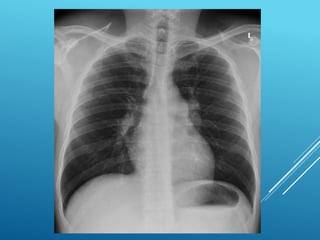

CXR CASE 1

 You suspect heart failure. What tests would you

order?